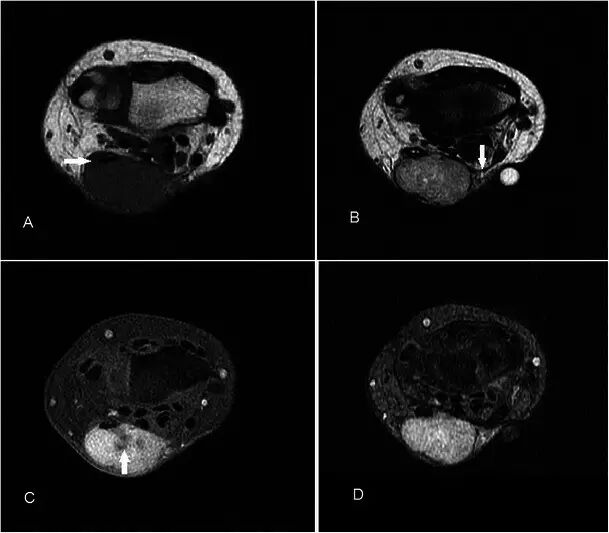

血管瘤 Haemangiomas 血管瘤是第四最常见的手部肿瘤,通常发生在年轻的年龄组,有轻微的女性优势[27]。在MR上,它们通常在T2w序列上非常高信号,并且显示出小叶,间隔或低信号灶比其他软组织块更频繁[28]。 T2w序列上损伤的标记高度信号是由于血管中停滞血流量增加的流体含量。 由于存在脂肪和血液成分,T1w序列上的信号通常与肌肉相比具有高信号(图8)。 通常大于2cm的损伤含有不同量的脂肪,平滑肌,粘液样基质,血栓和血铁素。上的GRE序列容易产生的假象可能是由于静脉石或血液成分引起,并且这些可以在平片进行区分。较大的病变也可能表现出流体 - 液体水平[29]。延时增强后瘤体趋于均匀强化。浅表性血管瘤易于诊断,因为皮肤褪色的存在,并且MRI可能仅需要评估其手术规划的程度。

图8.32岁女性血管瘤,沿着右手掌侧的内侧面呈现软肿块,偶尔会疼痛。 (a)T1w序列显示多发性皮下病变,小鱼际肌稍高信号肌肉,相邻肌腱(箭头)之间, 有一个小的肌肉内占位(箭头)。 (b)病灶在具有低信号(箭头)区域和流体 - 液体水平(箭头)建议的T2w-FS序列上是极度高信号的。 (c)看到显示静脉石或血制品(箭头)GRE序列。 (d)有积极和接近均匀的增强(箭头)